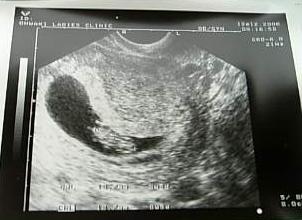

9weeks4days

9weeks3days

9weeks2days